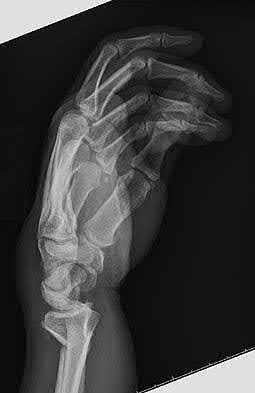

A 51-year-old female presents with an acute inability to extend her thumb, four months after she was treated with cast immobilization for a minimally-displaced distal radius fracture. What is the most appropriate treatment at this time?

A rare complication of non-displaced or minimally displaced fractures of the distal radius treated with a cast is a delayed rupture of the extensor pollicis longus (EPL) tendon. The EPL is the primary extensor of the interphalangeal joint of the thumb and also assists with metacarpophalangeal extension.

Extensor indicis proprius transfer to the EPL is the most widely used and reported treatment for this condition.

Magnussen et al. reviewed results of EIP transfer following ruptures of the EPL, with 19/21 good results. None of the cases had any loss of independent index finger extension although index extensor strength reduced to half of that of the contralateral side.

Hove et al. reported a similar satisfaction rate following treatment of 15 patients. In his series of 4,400 distal radius fractures treated over a 5 year period, the incidence of delayed tendon rupture following distal radius fracture was 0.3 percent.